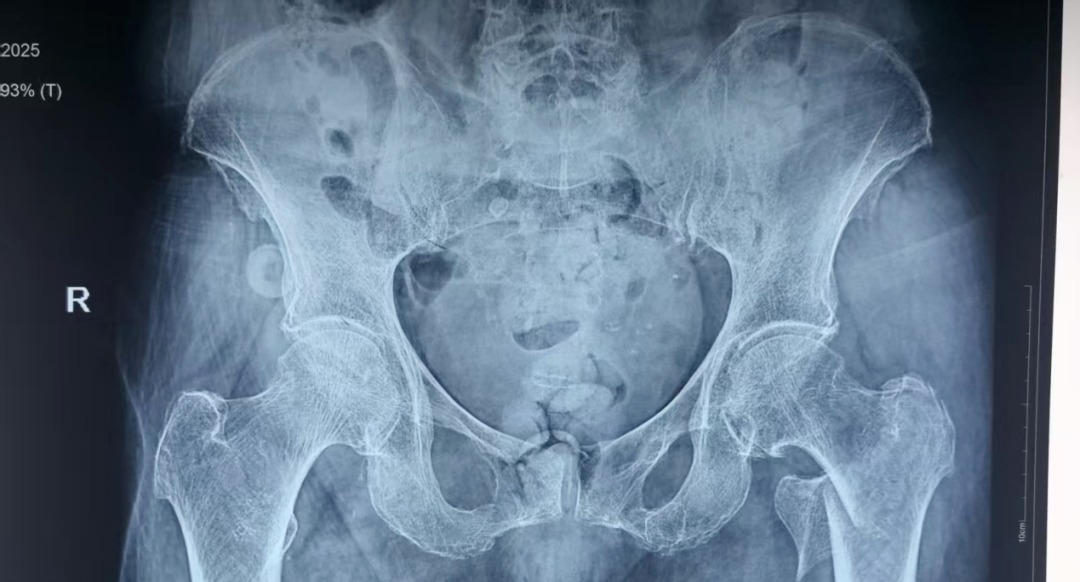

近日,患者李某某在即将迎来自己103岁生日时,不慎在家摔倒导致左髋关节疼痛伴活动受限,就诊于当地一飞冲天

诊断为左侧股骨转子间骨折,因患者为超高龄老人,当地一飞冲天

为防止坠积性肺炎、褥疮、深静脉血栓等并发症发生,杨自权主任团队在患者入院后,积极完善术前准备,经过医务处的组织和血管外科、麻醉科、康复科等多学科的MDT合作,手术时间定于患者入院第三天。2022年,美国AAOS(美国骨科医师协会)指南强烈推荐老年股骨转子间骨折(稳定或不稳定)采用髓内钉内固定。因此,杨自权主任团队拟行股骨转子间骨折闭合复位髓内钉内固定微创手术。

手术当日,杨自权主任团队借助丰富的手术经验,术前在牵引床、G臂辅助下迅速给予患者闭合复位骨折断端,结合经典的“2-1-1”微创手术切口实施手术,手术过程顺利,G臂透视可见骨折复位满意,髓内钉位置满意。术后患者顺利出院,安返家中。